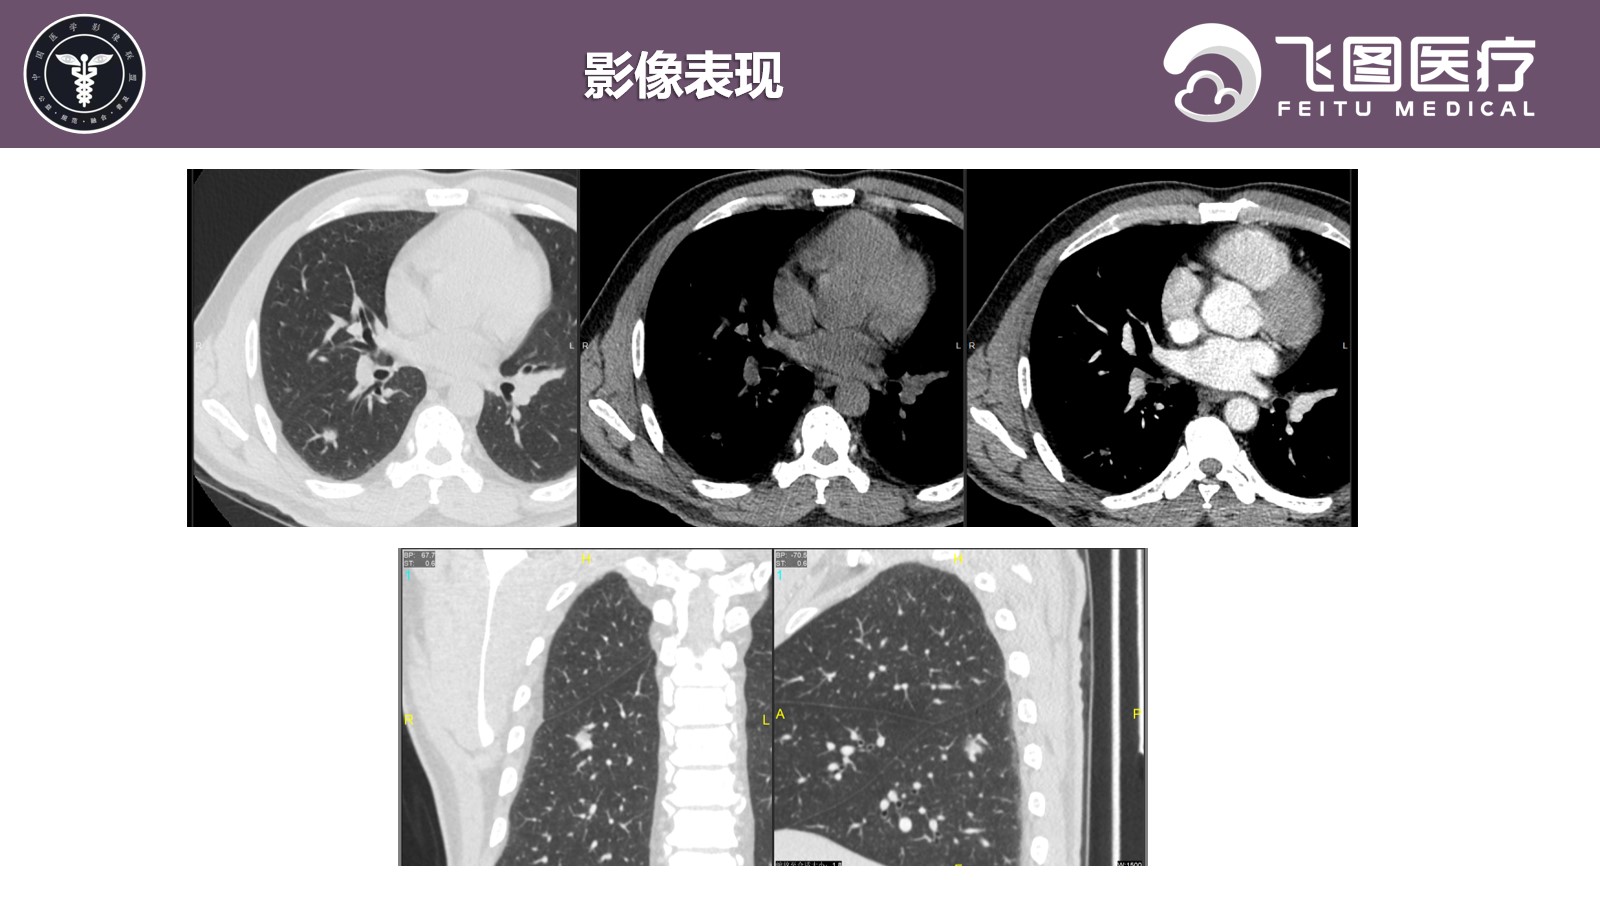

患者,男,50岁,因“检查发现右上纵隔肿物1月余。”入院。

现病史:患者于1月余前因“胆囊结石并胆囊炎”于我院治疗。查胸部X片提示右肺尖区斑片状密度增高影,倾向后纵隔来源占位性病变。患者平素无咳嗽、咳痰,无胸闷、气促,无呼吸困难等。

既往史:因“胆石症”行“腹腔镜下腹腔粘连松解+胆囊切除术”,术后病情较前好转,复查无异常,出院诊断: 1.胆囊结石伴有急性胆囊炎; 2.胆囊息肉; 3.黄疸; 4.肝功能检查的异常结果; 5.纵隔肿物; 6.肺结节; 7.脾大; 8.轻度贫血。